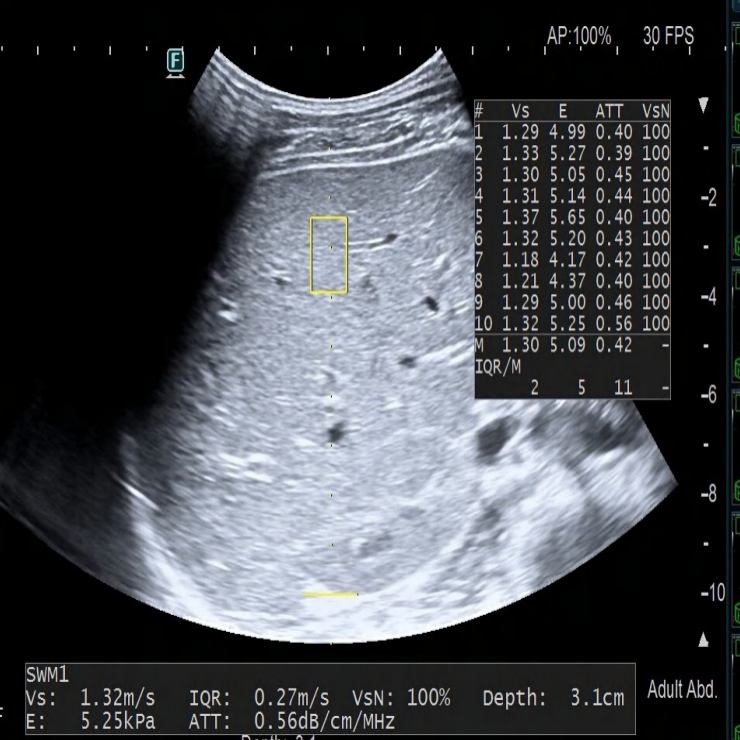

(健康儿童(左图)与脂肪肝儿童(右图)的肝弹性超声图像)

温馨提醒:有时候娃儿肝脏发炎、肚子胀气厉害,可能会影响报告结果,所以千万别仅凭报告上的数字,就判断娃的病情,一定要听医生的专业意见哦!